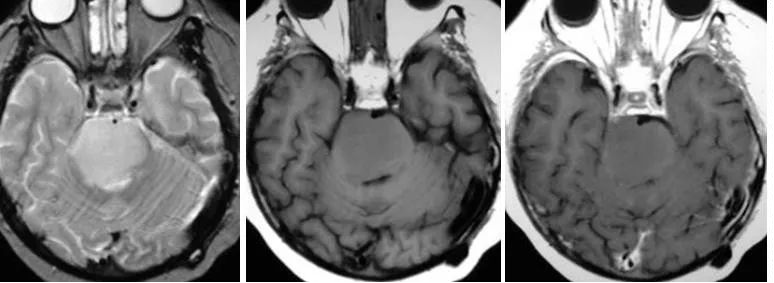

1、腦干毛細胞型星形細胞瘤:兒童患者較常見的神經膠質腫瘤,也是較常見累及小腦的腫瘤。值得一提的是該腫瘤有良性的生物行為,10年生存率達94%,大部分發(fā)生于20歲以前患者。小腦、視神經、視交叉及下丘腦是較常見的發(fā)病部位,但是該腫瘤也可發(fā)生于大腦半球、腦室及腦干。MRI通常表現(xiàn)為囊性腫塊伴壁結節(jié)強化,有時候也表現(xiàn)為實性腫塊無瘤周水腫,在腦干,其通常累及中腦及延髓,而浸潤型膠質瘤通常累及腦橋。

(橫斷位T1WI示一低信號腫塊累及腦橋延髓交界區(qū),T2WI及FLAIR呈高信號;橫斷位、冠狀位、矢狀位T1WI C示片狀、不規(guī)則形強化)

(矢狀位及橫斷位T1WI示中腦及腦橋上部見一囊性腫塊伴壁結節(jié))

浸潤性腦干星形細胞瘤:星形細胞瘤通常位于腦的某些區(qū)域,在成人,浸潤型星形細胞瘤通常位于大腦半球(75%),在兒童,浸潤型星形細胞瘤通常位于腦干,毛細胞型星形細胞瘤通常位于小腦。浸潤性星形細胞瘤通常侵犯腦干,但導致其損害,它可以發(fā)生惡性轉化。

橫斷位T2WI及FLAIR示腦橋高信號腫塊,橫斷位及矢狀位T1WI C示一膨脹性腫塊累及腦橋并向中腦和延髓延伸,增強未見強化。